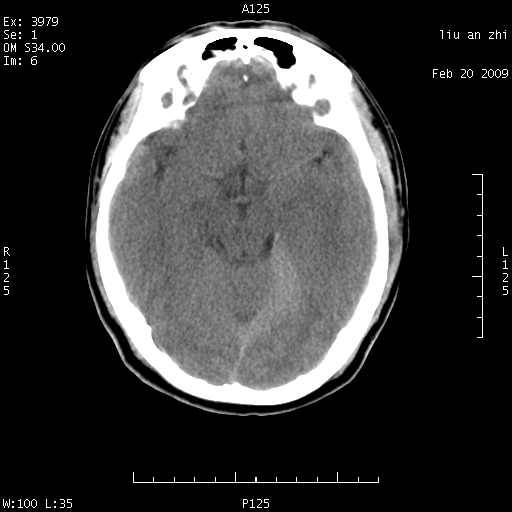

患者:男,32岁 被打伤后3天,自感头昏头痛作头颅ct检查。请大家看一下想什么??

7天后复查头颅ct片:

请注意小脑幕!!!

小脑幕前后7天变化不明显,考虑正常,不考虑sah,7天应该基本吸收了。

密度不够,不能诊断sah.正常小脑幕密度可稍高。

ct18448的结果:mri检查左侧天幕下血肿